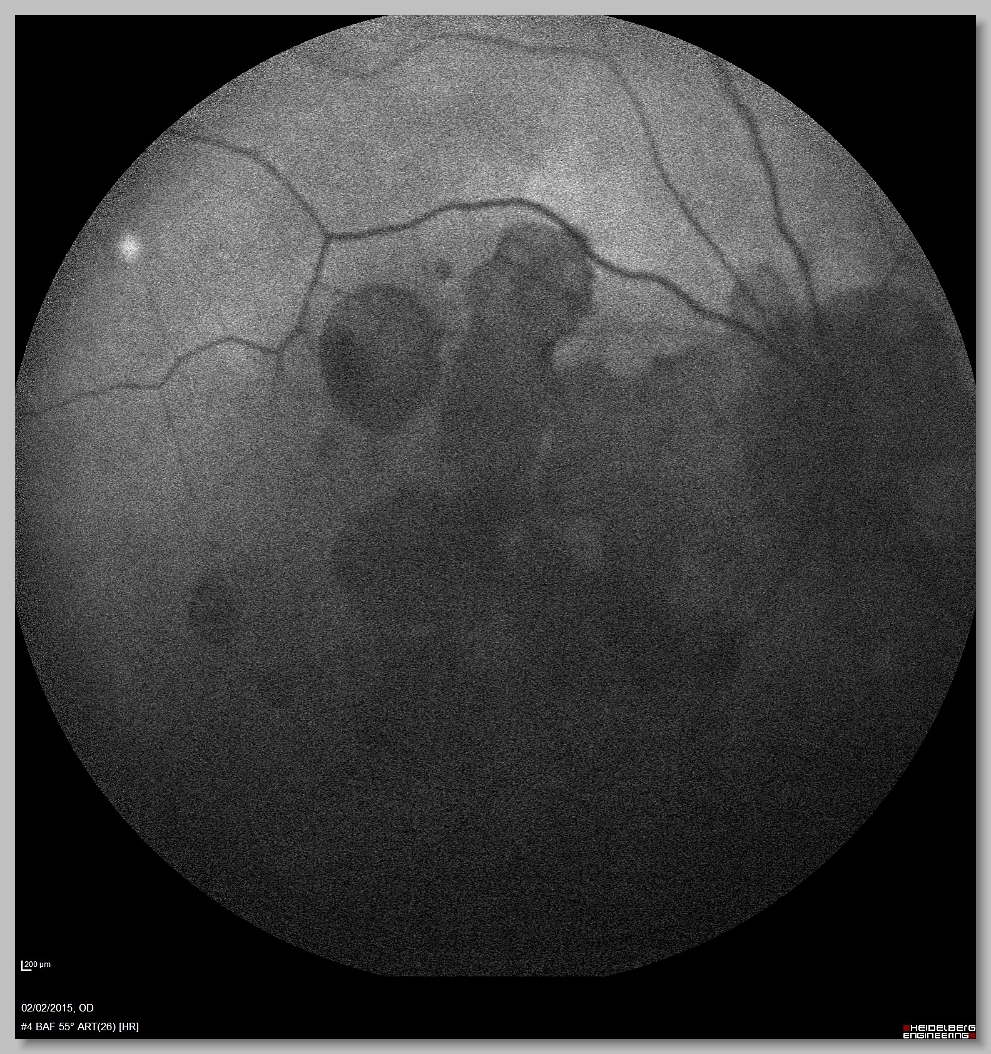

OCT 004 OCT 005 FA 000 FA 001